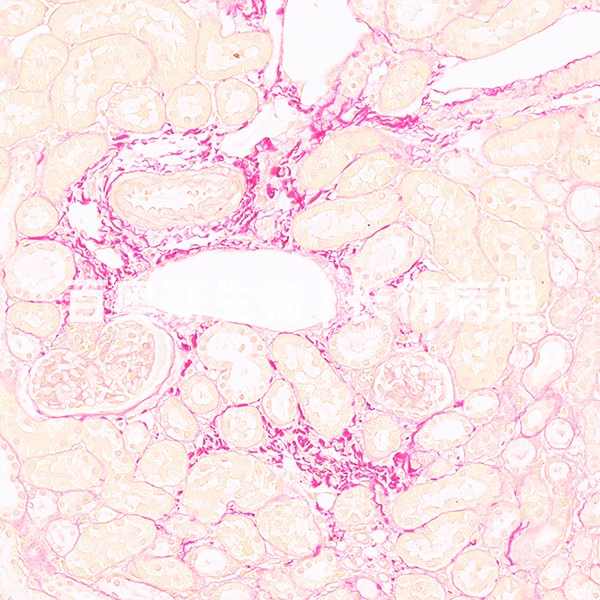

天狼猩红染色